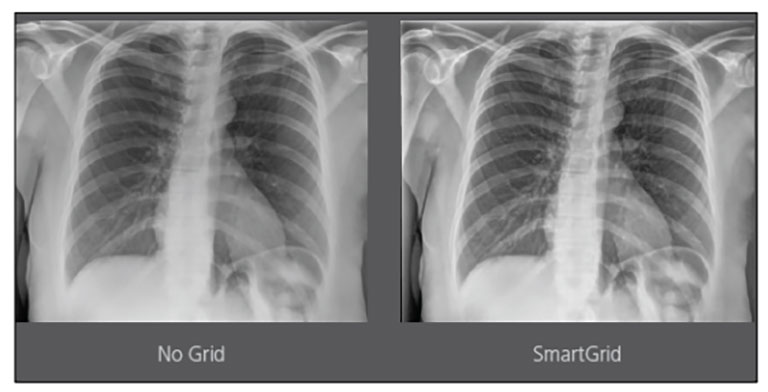

Carestream Introduces New Software Update to Boost Diagnostic Accuracy

Carestream today announced the latest update to its Image Suite V4 Software, MR 11: a series of enhancements to help improve customer confidence and increase diagnostic accuracy [...]